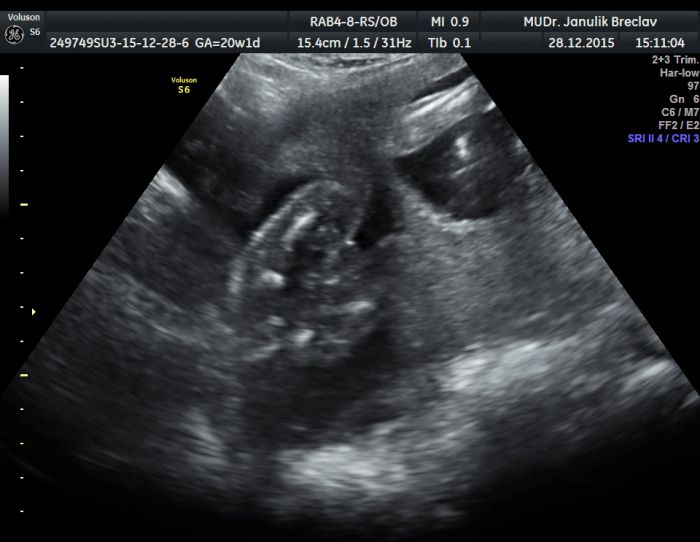

ahoj maminky chtěla bych se zeptat zda nekdo nepozna na fotce co by to mohlo byt :-D je to fotka z videa cekame pry jistou holcicku prvni jsem si myslela ze ej to pidnik :-D ale pri delsim zkoumani to pindik urcite neni ale nevim co jineho to je :-Ddekuji vam moc jinak jeste vkladam fotky kde by melo jit videt udajne kavove zrno ale ja ho nevidim :-Dtak snad tam ta holcicka je fotky jsou z ultrazvuku v 20+3

je to světlé. .. takže co stýská kost?... no pindik to není určitě :D

holku pokud to bude ta holcicka manzel se zblazni radosti :-) klucika uz doma mame moc jsem si prali kluka a ted holku ...samozdrejme ze kdyby to byl kluk nic se nedeje :-) ja od zacatku pocitala prave s klukem tak jsem docela v soku ze by se nam ta holcicka povedla ...bdu teda verit dr a tesi se na holcicku :-) ale co to tam je fakt netusim jeste me napadl klitoris ze pry ho muzou mit jeste natekly ale ze by az tak :-D:-D to asi ne :-D

[831384] Lukajdo,ale jo.Pokud Ti rekli dr. holcicku,bude to urcite klitoris.V tehle casti vyvoje ho holcicky jeste nemaji zakraty stydkymi pysky,ale prave takhle trcici ven,proto si laici muzou myslet,ze holcicka je vlastne chlapecek:-)